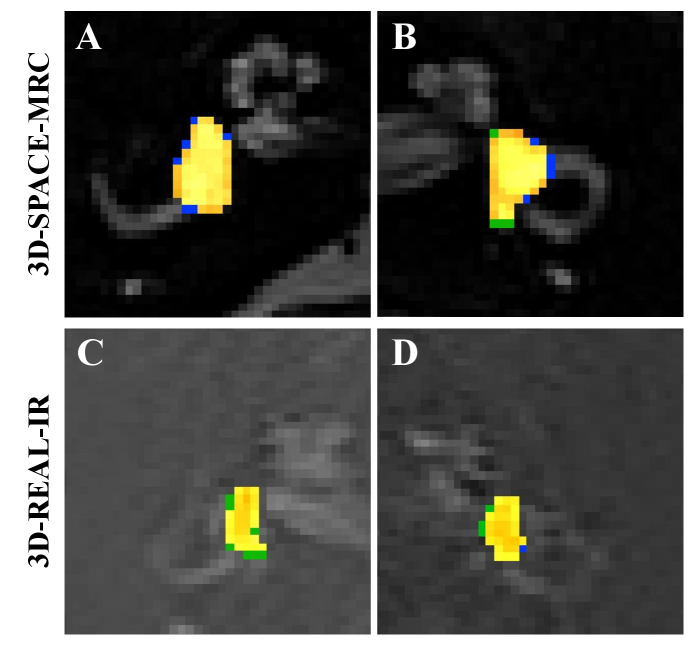

Representative examples in Fig. 4 illustrate the close alignment between predictions and manual annotations. Most errors occurred in low-contrast slices or regions affected by partial-volume artifacts. Overall, EHMasker achieved robust performance, particularly for SPACE-MRC (Dice ¿ 0.9), and maintained reliable sensitivity in REAL-IR, validating the U-Net with BCE+Dice loss and the adopted training strategy as an effective approach for automated segmentation of the endolymphatic space.

Refer to caption

Figure 4: Qualitative segmentation examples for both modalities. Panels A–B: 3D-SPACE-MRC; Panels C–D: 3D-REAL-IR. The model prediction (green) and the ground-truth annotation (blue) are overlaid on the MRI slice; the overlap region is shown in yellow. These examples illustrate the close agreement between predicted masks and expert annotations across modalities.